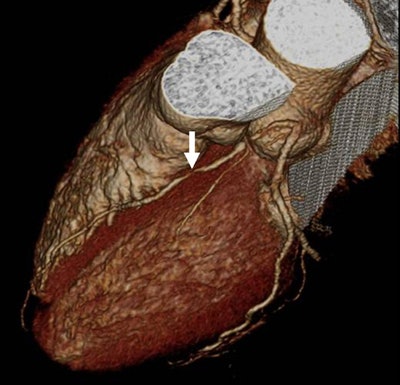

| Images 1-7 shown top to bottom: A 59-year-old man presented with atypical chest pain. A circumscribed, short-segment high-degree stenosis (arrow) in the proximal LAD is difficult to detect on transverse (1), sagittal (2), or coronal (3) multiplanar reformats. Use of advanced visualization tools with automated extraction of the coronary artery tree (4) and automated display as curved multiplanar reformat (5) clearly identifies the lesion, also seen in the 3D view (6) and confirmed on conventional catheter angiography (7). All images courtesy of Dr. U. Joseph Schoepf. |